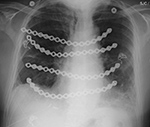

Figure 35A Figure 35B

PA Chest radiograph (A) demonstrates a sternal cage. Whole body Tc99m MDP images (B) demonstrate focal radiotracer activity in ribs bilaterally on the anterior view representing the sites of sternal cage fixation with bony reaction.